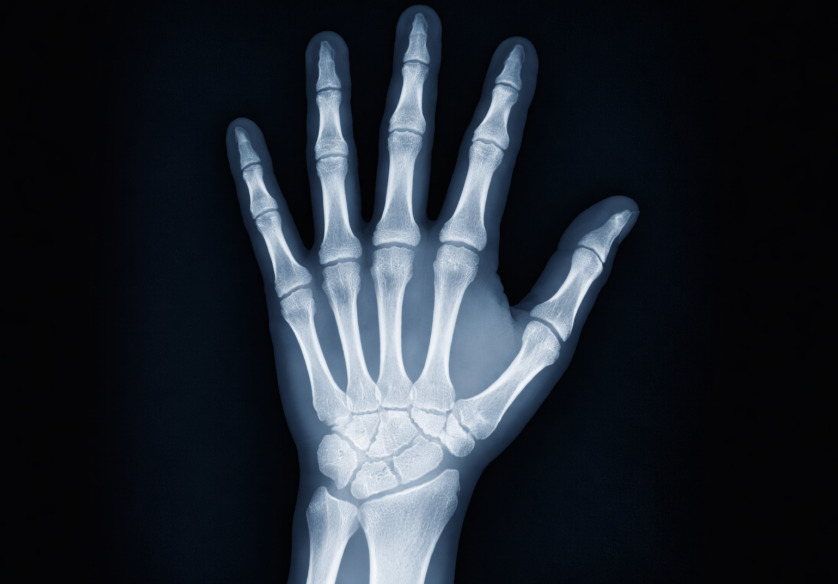

O hábito de estalar os dedos pode causar artrite? Veja se é mito ou verdade